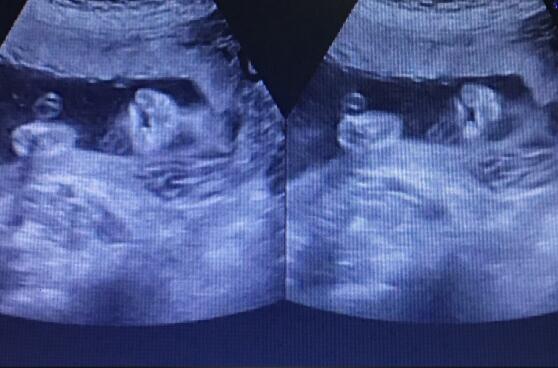

5月12日,正值母親節(jié),本是象征著愛意和美好的一天,但孕21周的二胎孕媽黃女士在武漢仁愛醫(yī)院做四維大排畸檢查時卻收到了一個晴天霹靂。 胎兒嘴唇上有裂縫,為唇裂?!ぁぁ?/p> read more